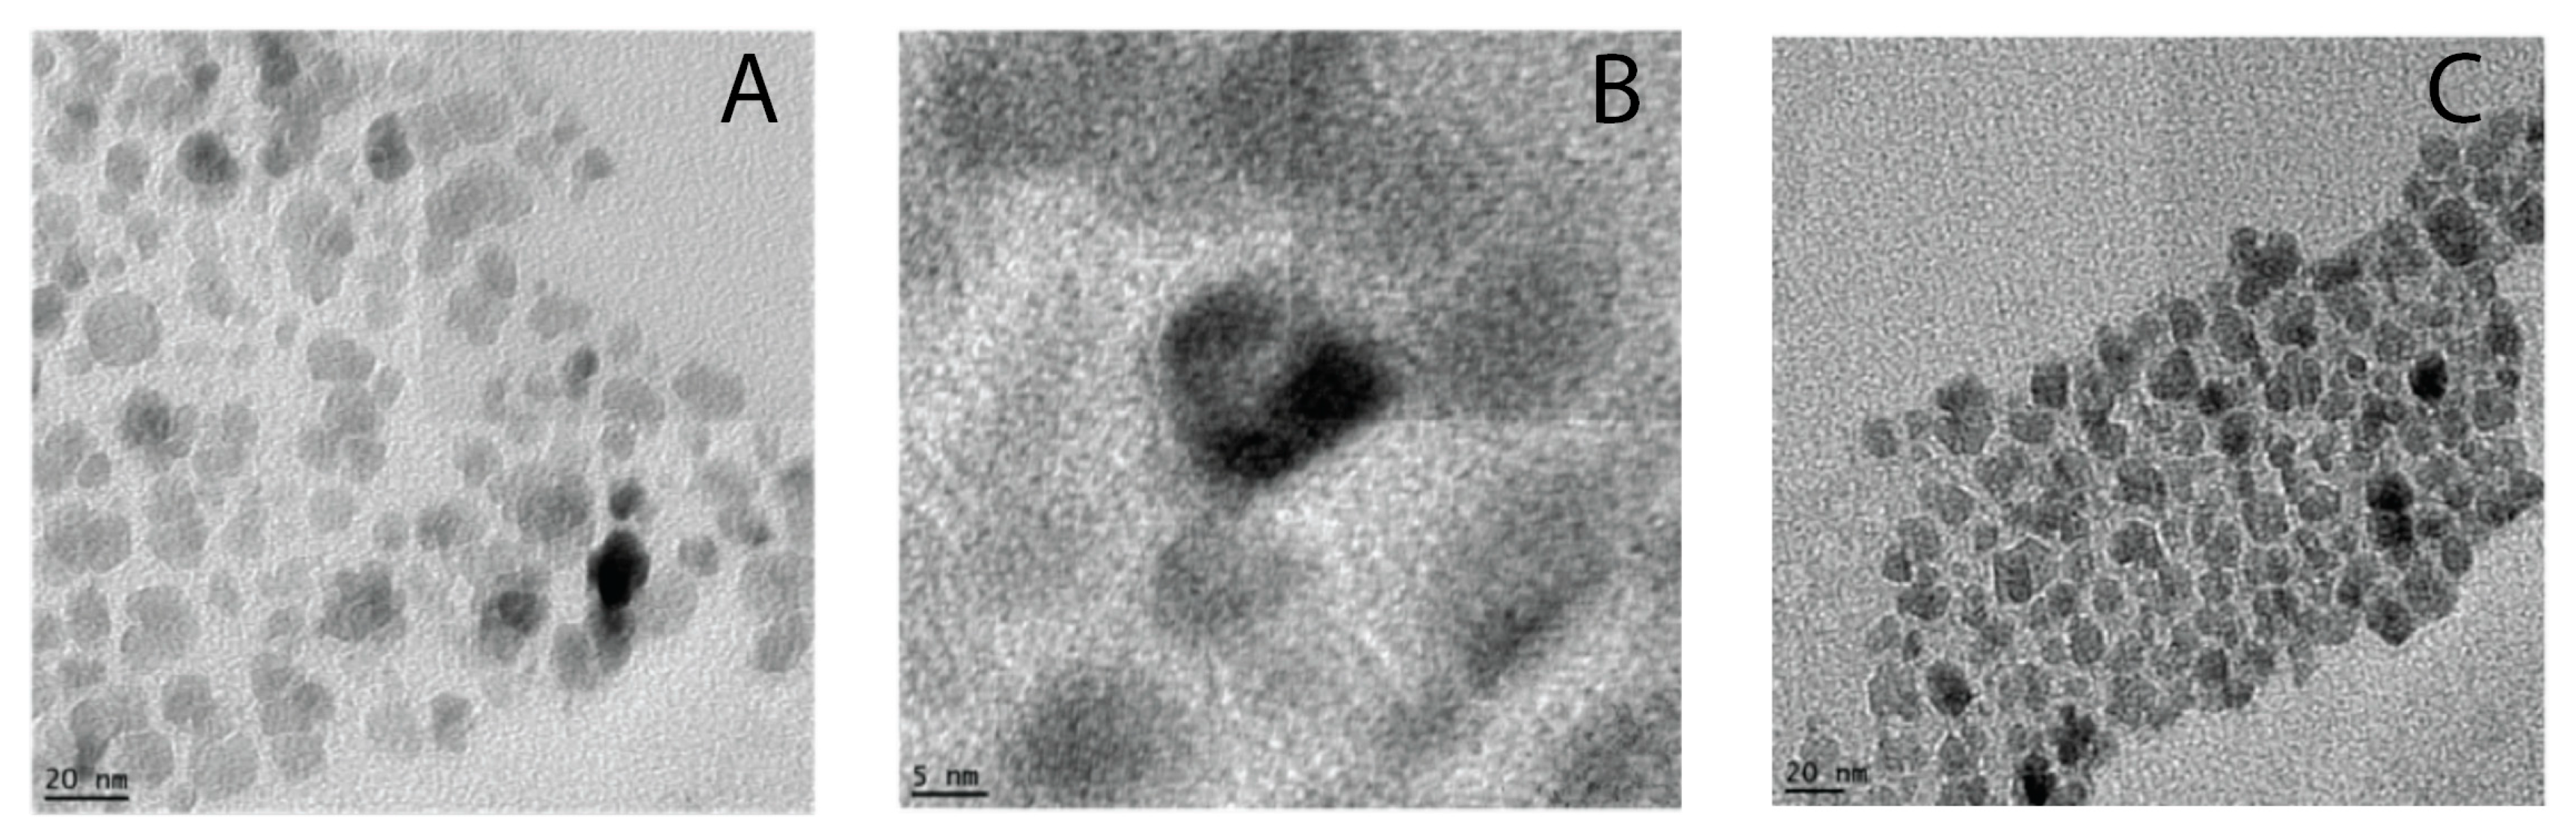

3.1. Synthesis of Pluronic F127- Folate coated and F127 coated SPION

3.2. Particles Size and Zeta Potential

3.2.1. Size of Particles